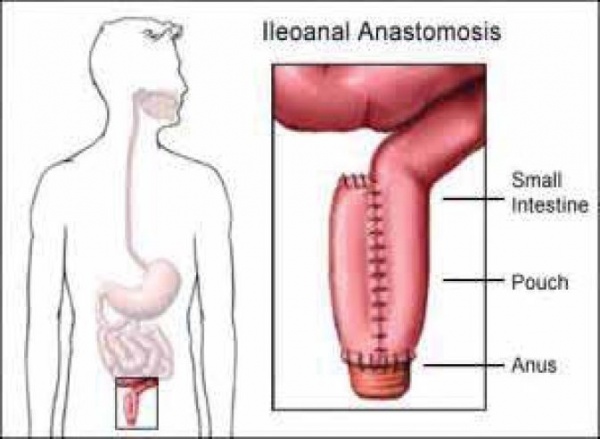

- כריתה תת-שלמה של המעי הגס עם השארת רקטום והשקה (חיבור) בין הרקטום למעי הדק (subtotal colectomy with ileorectal anastomosis - IRA)

- כריתת כל המעי הגס והרקטום (total proctocolectomy) עם חיבור בין המעי הדק לפי הטבעת ויצירת מאגר (פאוץ') מלולאת מעי דק לשם יצירת "מכל " דמוי רקטום -ileo-anal pouch (תמונה מס' 2) [4]

קיים ניסיון רב שנים בניתוחים אלה, והם מבוצעים גם בגישה פתוחה וגם בגישה לפרוסקופית. הבחירה בין הניתוחים תלויה במגוון שיקולים, ובעיקר בעומס הפוליפים ברקטום, ברקע הרפואי, בהעדפת המטופל, בניסיון המנתח ועוד. כריתה תת-שלמה של הרקטום מאפשרת צמיחה עתידית של פוליפים בגדם הרקטום, שניתנים לרוב להסרה אנדוסוקפית. עם זאת, ניתוח פאוץ' הוא נרחב יותר, ולעיתים מעלה את הסיכון לגידולי דסמואיד שעשויים לסכן את הפאוץ'.